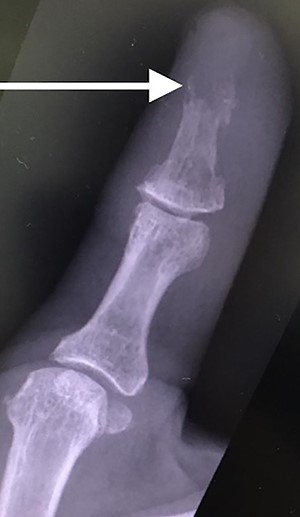

The patient was then reviewed 6 weeks after her initial presentation, following the results of the sarcoma MDT, which confirmed a benign tumour. At this point, the patient reported some tenderness around the surgical incision, but that her symptoms were improving. It was thought that she had no signs of ongoing infection in the thumb. The outcome was for monitoring of her symptoms with no indication for surgical excision. She had a follow-up X-ray in 6 weeks’ time that showed resolution of the lytic lesion (Figs 6 and 7).

AP follow-up radiograph of right thumb 6 weeks post-admission showing resolution of lytic lesion.